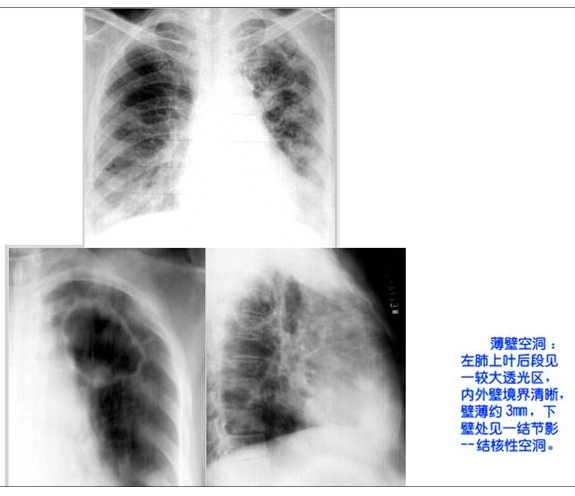

照片名称:薄壁空洞